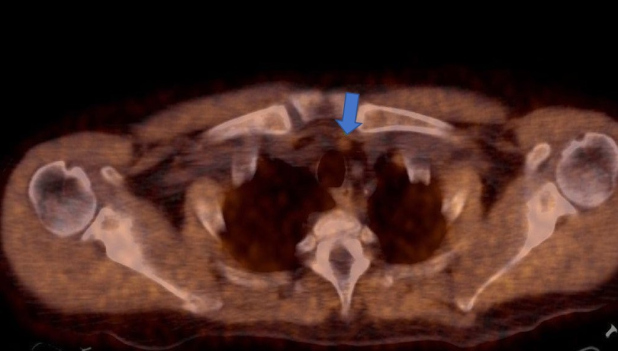

Paciente de 72 años con insuficiencia renal crónica en plan de trasplante, con cirugía previa de paratiroides. Por valores elevados persistentes de PTH y ante resultados confusos del centellograma con 99m Tc- sestamibi, se realiza PET-CT con 18F-Colina para detectar presencia de tejido paratiroideo hiperfuncionante. En el estudio híbrido morfo-molecular se evidencia imagen nodular de 17 mm en región ínfero medial cervical anterior con aumento de la captación del radiotrazador (SUV máx. 3,5) consistente con tejido paratiroideo (fig. 3). Además, se detecta una lesión predominantemente lítica e hipercaptante de 26 mm de diámetro en la espina del omóplato izquierdo, que cursaba en forma asintomática (fig. 4, arriba). Se realiza biopsia de la misma, dando como resultado tumor pardo (fig. 4, abajo).